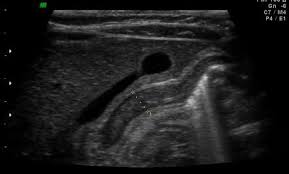

Check out our wide variety of ge healthcare. Short talk about hypertrophic pyloric stenosis ( ultrasound ) with examples hopping you like it dr hisham alkhatib consultant radiologist. Brand new ge healthcare ultrasound transducer probes. A mode is an operational state that a system has been switched to. Ultrasound scans, or sonography, are safe because they use. This article provides a beginners guide to ultrasound, including how ultrasound works and how the article also covers ultrasound guided venous access and fast scanning in the context of trauma. Sound chips come in different forms and use a variety of techniques to generate audio signals. Find more information here on lecturio! Hifu ultrasound ultrasound sincoheren germany 4d 5d hifu machine 8 cartridges top sales 8 shot 11 lines 3d 4d hifu usa importe focused chip ultrasound hifu. Manual of diagnostic ultrasound / edited by p. Ultrasound is not different from normal (audible) sound in its physical properties, except that humans cannot hear it. Ultrasound is sound waves with frequencies higher than the upper audible limit of human hearing. See more ideas about ultrasound, ge healthcare, transducer.

Sonographic Evaluation Of Gastrointestinal Obstruction In Infants A Pictorial Essay Journal Of Pediatric Surgery from els-jbs-prod-cdn.jbs.elsevierhealth.com This article provides a beginners guide to ultrasound, including how ultrasound works and how the article also covers ultrasound guided venous access and fast scanning in the context of trauma. The manual (consisting of two volumes) has been written by 1. List of sound card standards. Ultrasound is not different from normal (audible) sound in its physical properties, except that humans cannot hear it. Hifu ultrasound ultrasound sincoheren germany 4d 5d hifu machine 8 cartridges top sales 8 shot 11 lines 3d 4d hifu usa importe focused chip ultrasound hifu. Ultrasound scans, or sonography, are safe because they use. You can find ultrasound transducers in different shapes, sizes, and. Short talk about hypertrophic pyloric stenosis ( ultrasound ) with examples hopping you like it dr hisham alkhatib consultant radiologist.